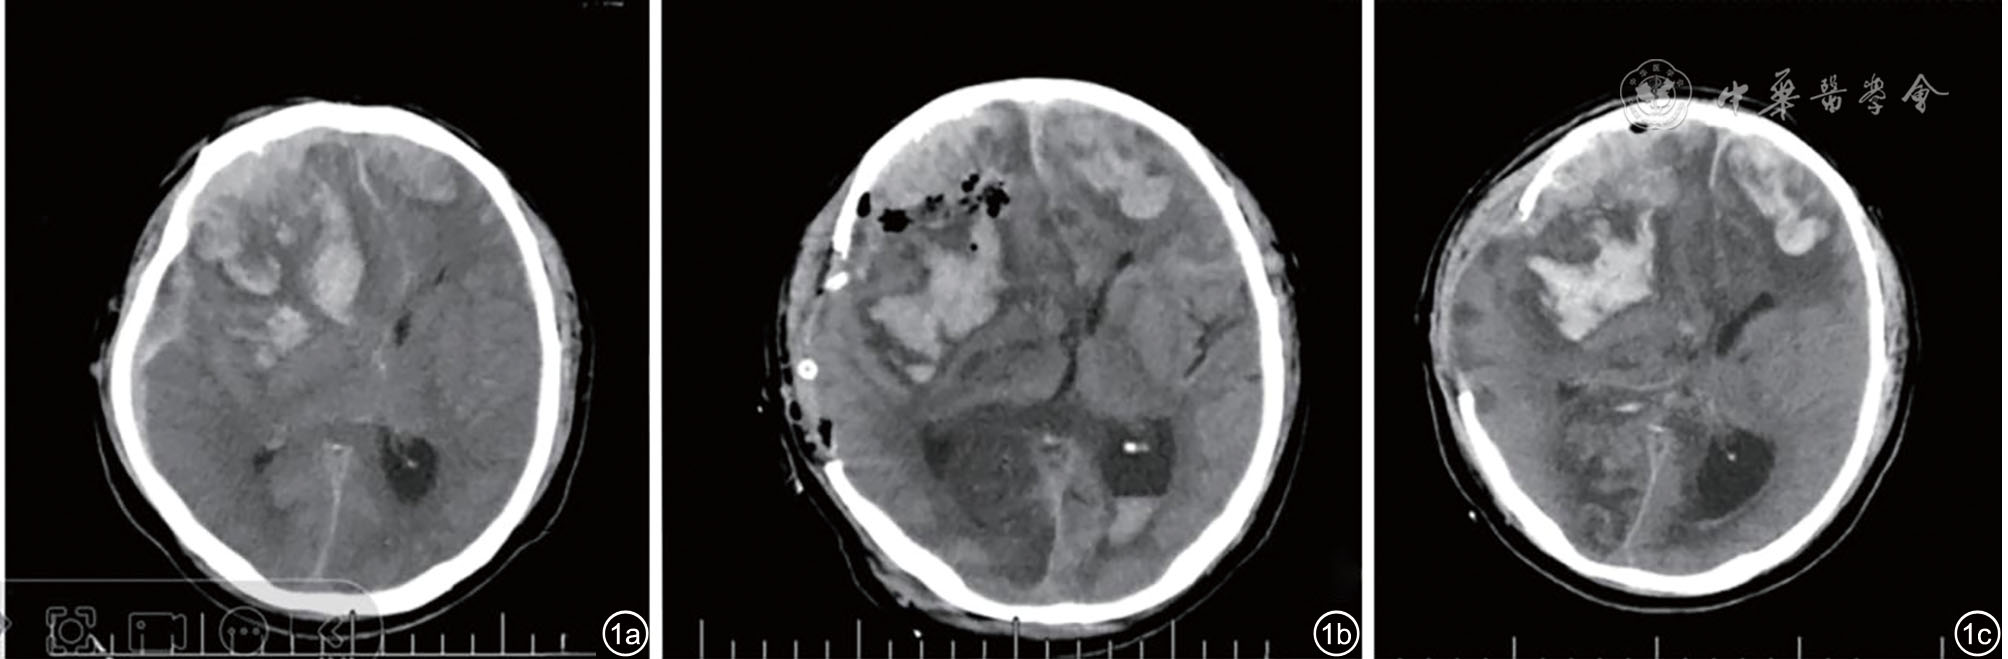

图1 患者颅脑CT检查(局部幕上切面)。图1a为入院当天(术前);图1b为入院当天术后:可见左额积血较前增多,右顶枕叶、双侧胼胝体压部新发低密度梗死灶;图1c为术后第5天:脑内低密度范围较前无显著变化,脑疝,脑组织弥漫性肿胀